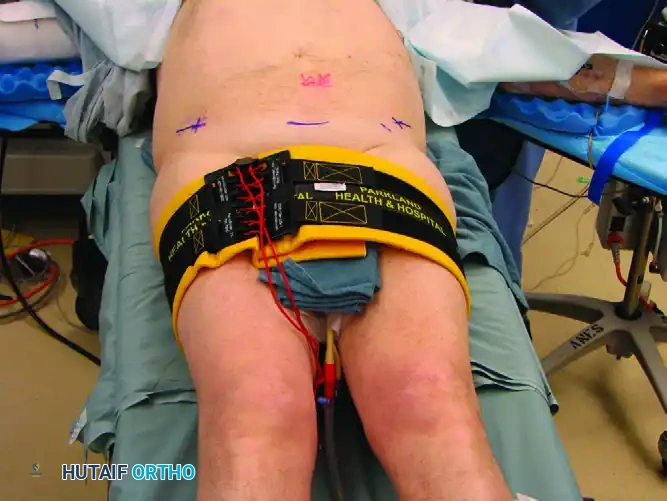

The Circumferential Pelvic Binder

Upon clinical or radiographic recognition of an unstable pelvic ring injury, the immediate application of a circumferential pelvic binder is routine. First described in the literature by Routt et al., this technique involves wrapping a bed sheet or a commercially available binder around the pelvis.

Application Technique:

1. The binder must be centered directly over the greater trochanters, not over the iliac crests or abdomen.

2. Circumferential tension is applied to internally rotate the hemipelves.

3. The binder is clamped or secured via its proprietary mechanism.

Mechanism of Action:

Binding theoretically reduces intrapelvic volume, stabilizes raw bleeding fracture surfaces, and encourages retroperitoneal tamponade. In the acute resuscitation stage, circumferential pelvic binding is preferred over external fixation due to its ease, non-invasiveness, and rapid application. Croce et al. demonstrated a significantly decreased need for blood transfusions following the implementation of institutional binding protocols.

Pitfall: Placing the pelvic binder too high (over the iliac wings) can paradoxically open the true pelvis further, exacerbating hemorrhage and worsening the deformity in lateral compression injuries.